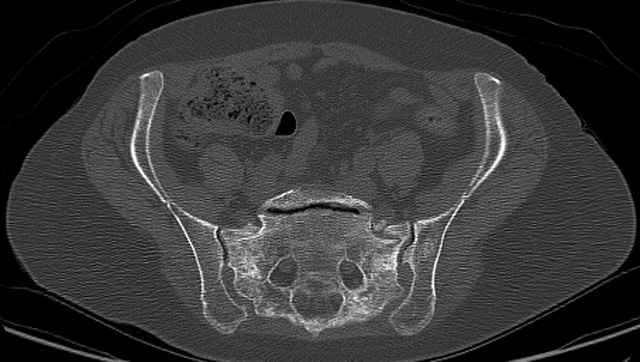

Pelvic CT Scan - 3 Months After Fall

Sacral Injuries

Ramus Fractures